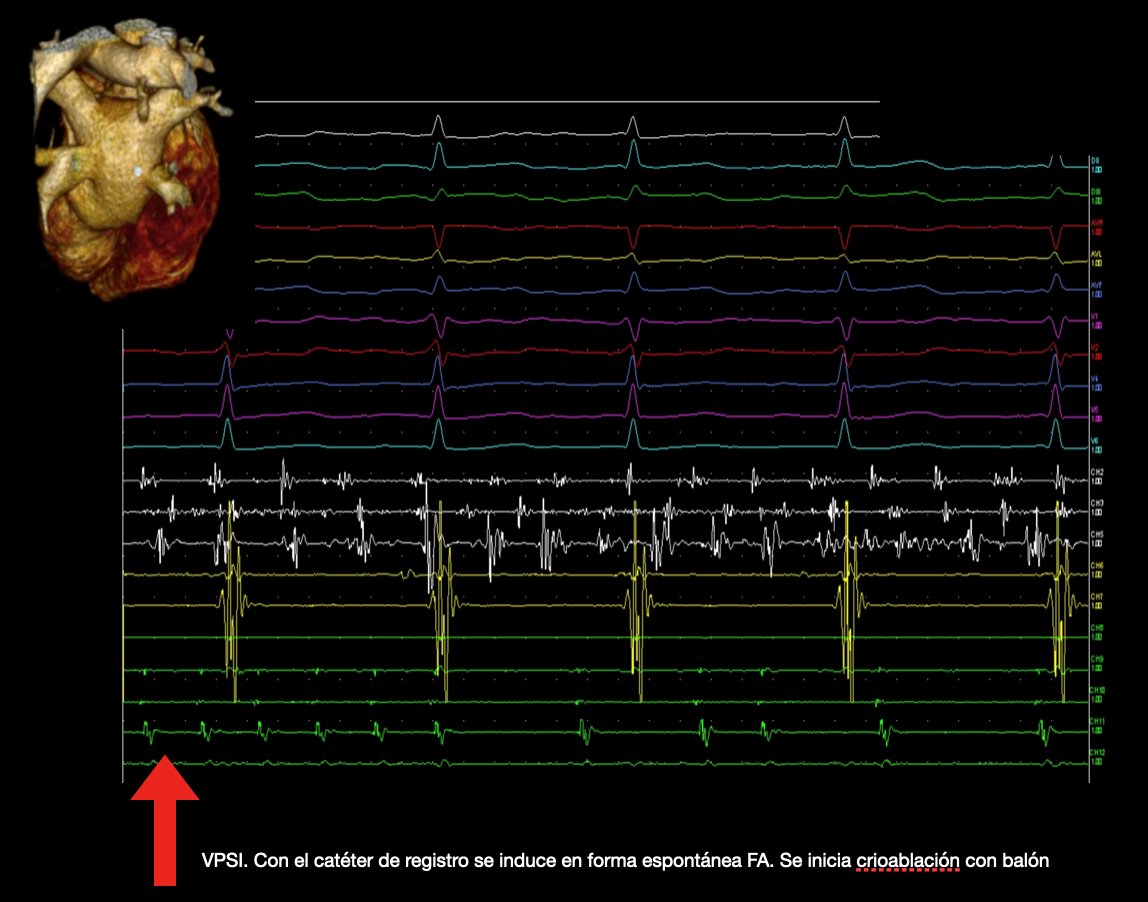

Pulmonary Vein Cryoablation in Argentina. Hospital HIGA San Martín